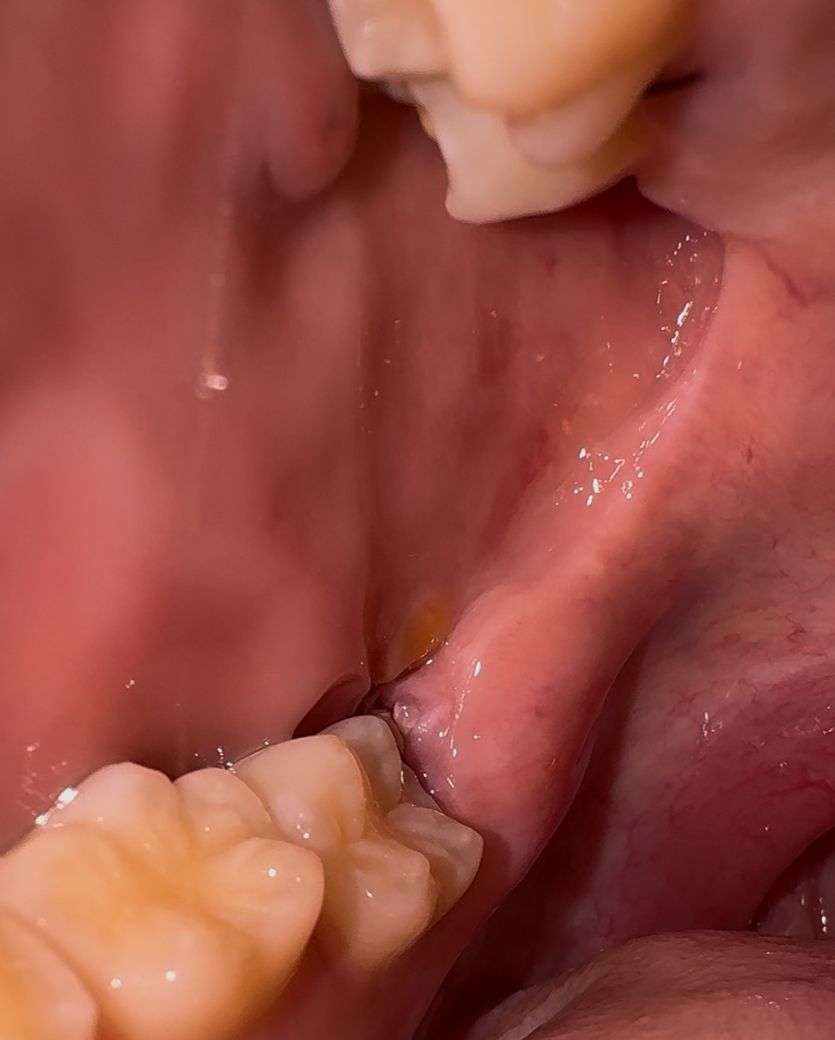

사랑니 발치 4일차입니다. 상태 어떤가요?

안녕하세요. 13일 수요일 오후에 아래 수평매복사랑니하고 위 그냥 사랑니 발치하고 현재 상태입니다. 통증은 따로 느껴지는거 없는데 사진상으로 볼때 상태 괜찮은거같나요?

사진상으로는 문제 없이 잘 낫고 있어보입니다. 지금처럼 관리 잘해주시면 될 것 같습니다.

사진상으로 발치한곳을 보면 크게 문제가 되는건 없어 보입니다. 걱정하지 않으셔도 될것같습니다.

사진으로 봤을 경우에는 크게 문제가 있는 것으로 보이진 않습니다. 사랑니를 발치하고 나서 발치한 부위가 자극이 되면 출혈이 되고 치유가 늦어질 수 있으니 발치한 부위를 자극하지 않도록 하는 것이 좋습니다.